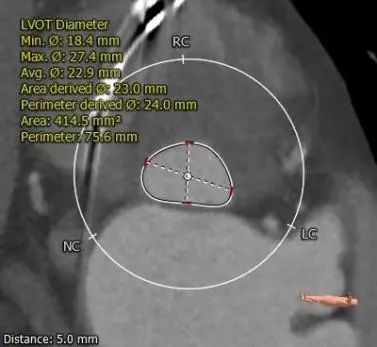

主动脉根部测量

瓣上测量

3.推荐22mm球囊预扩,根据球扩后腰征决定AV26还是AV29瓣膜,瓣环下2mm定位释放,建议释放后调整至右前斜足位 RAO 6 CRA 35 左右进一步确定人工瓣膜展开形态。